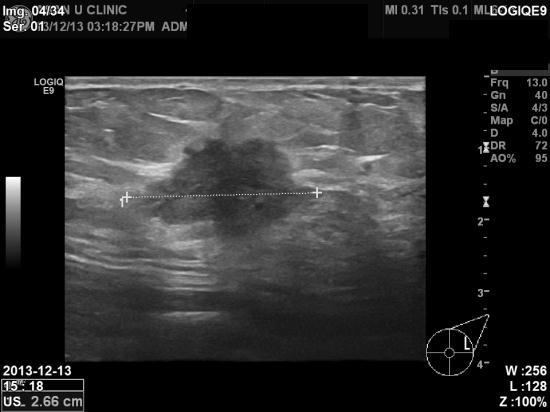

좌측 유방에 통증과 몽우리가 있어 내원한 45세 여성분입니다.

2012년 12월에 공단검진으로 유방촬영을 실시하였으며

이상소견 없었다고 기억하시는 분입니다.

본원초음파상 2.66cm의 혹이 있었으며, 조직검사상 침윤성 유방암으로 진단되었습니다.

1년전에 과연 없었던 것이 생겼을까요?

아니면 유방촬영상에 치밀한 정상유방조직사이에서 보이지 않았던 것일까요?

치밀유방이시라면 유방초음파로 확인을 해보는게 안전할 것 같습니다.